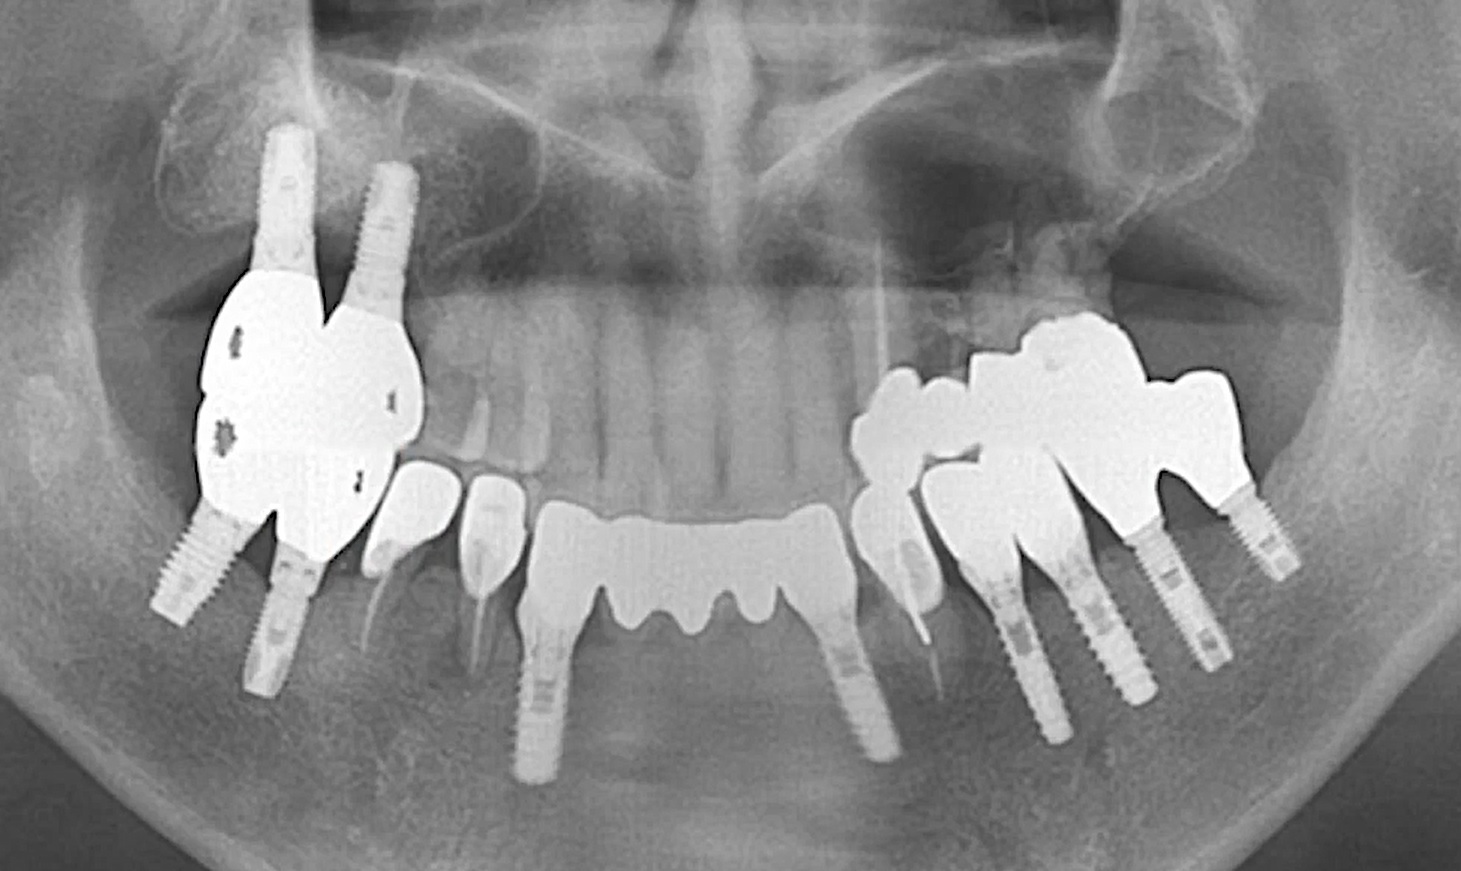

Dr Segin Chandran,Single replacement,Bone regeneration,Digital Guided Surgery,Maxillary Posterior,#25,Immediate Placement,Sinus Elevation,Guided surgery,AnyRidge,R2GATE Guide,R2GATE Surgical Kit(AnyRidge),MICA,Crestal elevation,Minimally invasive,Video